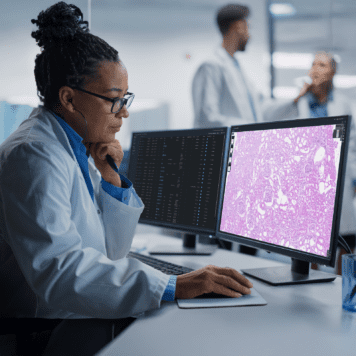

Our Anatomic Pathology workflow and AI platform was developed to provide pathology practices with a comprehensive digital pathology platform.

Techcyte Fusion AP is a comprehensive digital pathology platform that brings together all the stakeholders, use cases, patient information, and technology by digitizing those workflows and enabling the use of AI to increase the efficiency and accuracy of a pathology practice.

Techcyte does the hard work of integrating the EHR, LIS, PACS/VNA, scanners, storage, stain ordering, annotations, AI, messaging, worklist and reporting into an easy-to-use, modern, browser-based pathology workspace.